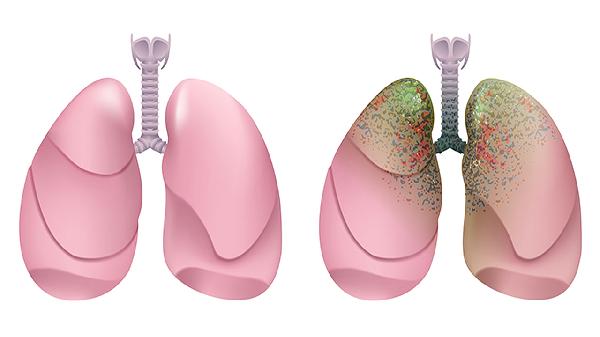

肺上出现气泡不一定会癌变,需要根据具体情况进行医学检查评估。肺气泡可能是肺气肿、肺大疱等良性病变的表现,但也可能是肺癌等恶性疾病的早期信号。治疗方式取决于病因,包括药物治疗、手术治疗和生活方式调整。

2、肺大疱是肺泡过度膨胀形成的囊状结构,可能与先天性因素或慢性阻塞性肺疾病有关。对于较大的肺大疱,可能需要手术切除,如胸腔镜手术或开胸手术,以减少破裂风险。

3、肺癌早期可能表现为肺部结节或气泡,需要进一步通过CT扫描、PET-CT或活检确诊。治疗方式包括手术切除、放疗和化疗,具体方案需根据肿瘤类型和分期制定。